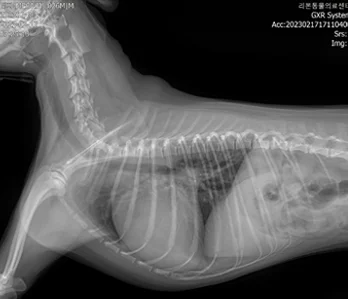

• X-RAY

영상의학과는 X-ray, 초음파, CT, MRI 등 다양한 첨단 장비를 활용하여 동물의 내부 상태를 영상으로 표현하고, 이를 기반으로 정확한 진단과 치료 방향을 제시하는 역할을 합니다.

• X-RAY 케이스 수 : 3만 9천건이상